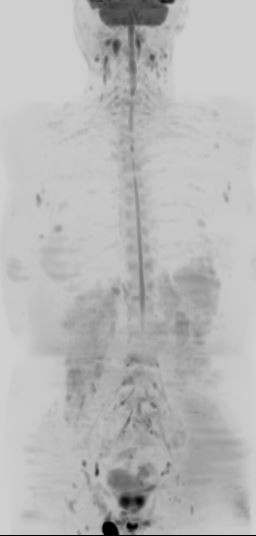

全身MRIがん検診(DWIBSドゥイブス検査)

「被ばくなし・30分で全身を確認」

全身MRIがん検診(DWIBSドゥイブス検査)とは

DWIBS(Diffusion Weighted Imaging with Background Suppression)人間ドックは、MRIを用いて全身のがんや病変を調べる検査です。

放射線被ばくがなく、体への負担が少ないことから、近年注目されている人間ドックの一つです。

CTやPET-CTのような放射線検査に不安がある方でも、安心して受けていただけます。

全身MRIがん検診(DWIBSドゥイブス検査)でわかること

DWIBS検査では、以下のような病変の発見に役立ちます。

■全身のがんの可能性

■リンパ節の異常

■骨・軟部組織の異常

など